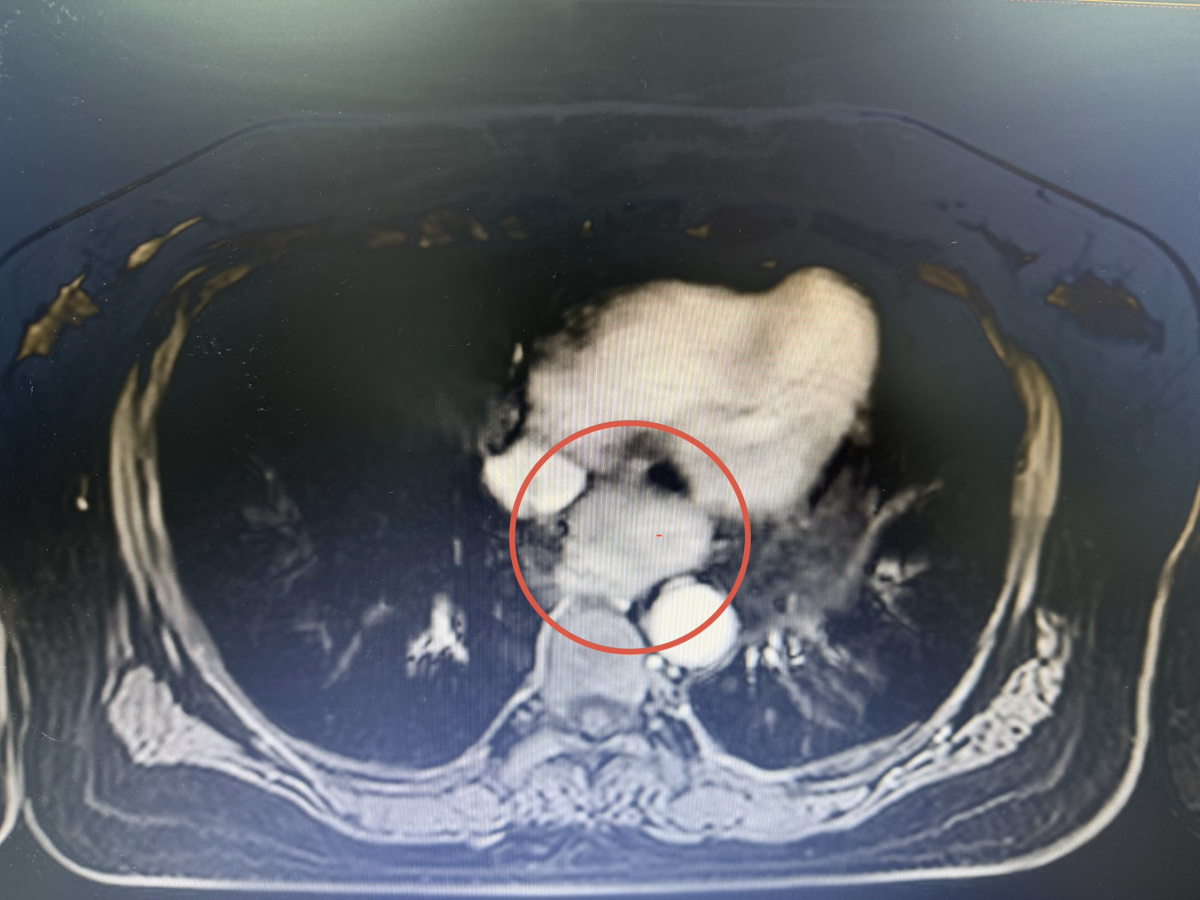

为进一步明确诊断,她来到河南省胸科医院,接受了胸部CT增强、纵隔MRI等检查。影像结果显示,病灶位于后纵隔食管胸下段前方,形态类似“葫芦”,大小约45mm×35mm,呈囊性,与食管左前壁分界欠清,右肺门区淋巴结存在增多增大的情况。综合影像学特征,临床高度怀疑为前肠囊肿等良性病变。

“这个位置的病变,就像一个紧贴在食管壁上的‘葫芦’,位置深、毗邻关系复杂。”河南省胸科医院胸外一病区副主任医师华胸怀介绍。纵隔是胸腔内两肺之间的核心区域,内含心脏、大血管、食管、气管及众多重要神经。此区域的肿瘤或囊肿早期常无症状,易被忽视。当病灶增大压迫邻近器官时,才可能出现咳嗽、胸痛、胸闷、吞咽困难或咯血等症状。